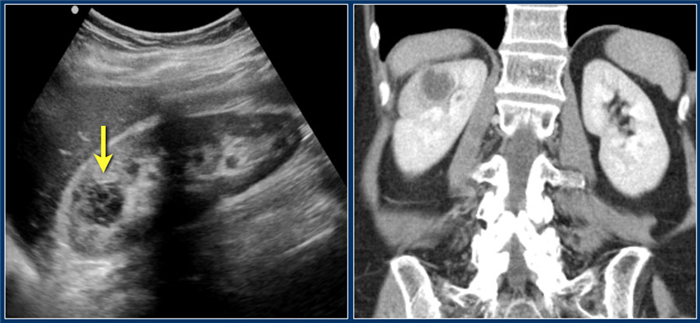

Этот пациент типичный поступил с болью в правом боку и изменениями в лабораторных данных, характерные для инфекции мочевыводящих путей.

На ультразвуковом изображении визуализируется гипоэхогенный очаг с гиперэхогенным включением, что соответствует на жидкостное включение.

Диагноз — абсцесс.